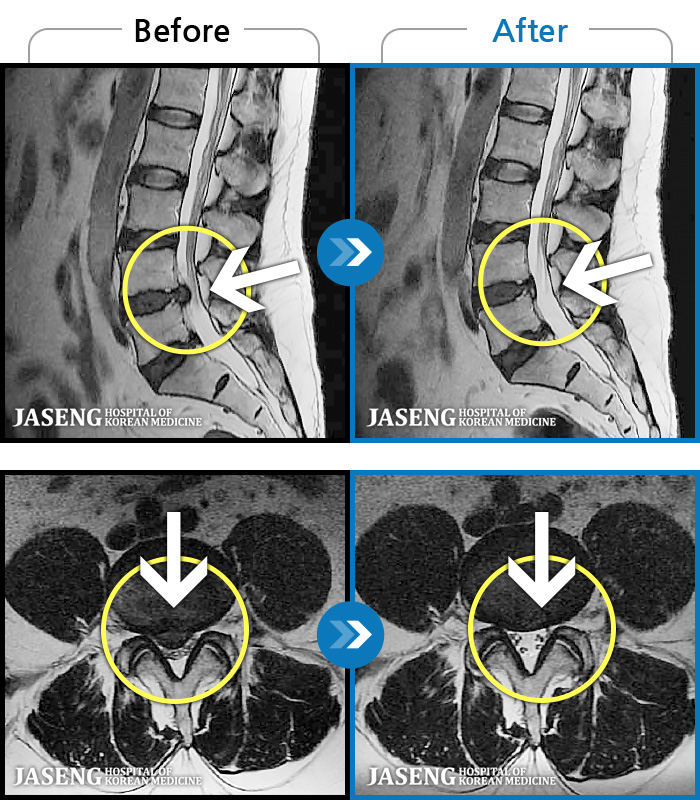

ó 㸮 , ٸ ϰ ־ Ȱ , ߰ ᵵ ڰ Ͽ Ȱ ¼̽ϴ. |